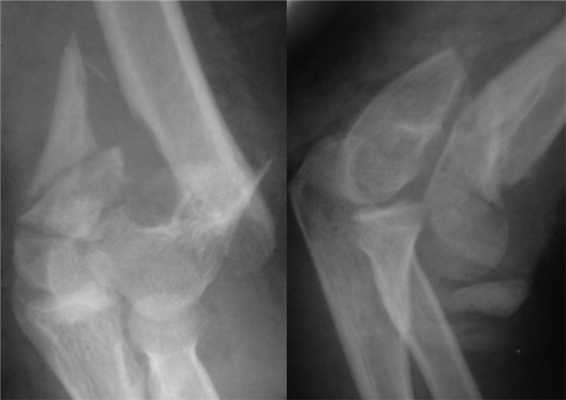

Больная П., 25 лет, поступила в стационар с жалобами на боли в левом локтевом суставе через 2 ч после травмы в результате падения на улице. При осмотре отмечены отек левого локтевого сустава, болезненность при пальпации, невозможность движений в суставе из-за боли. После клинико-рентгенологического обследования установлен диагноз: закрытый внутрисуставной оскольчатый чрезмежмыщелковый перелом левой плечевой кости со смещением отломков тип 13-С2 (рис. 2). Рисунок 2. Рентгенограммы больной П. с внутрисуставным оскольчатым чрезмежмыщелковым переломом левой плечевой кости со смещением отломков тип 13-С2.